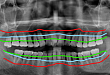

很多年轻患者来到牙科不清楚自己的牙齿状况,最常见的一个症状是牙龈出血,但由于不痛,很多患者觉得不是大问题。案例分析下图是一位 40+的中年患者,经牙科医生检查诊断为牙龈发炎、牙结石、牙槽骨萎缩及牙根暴